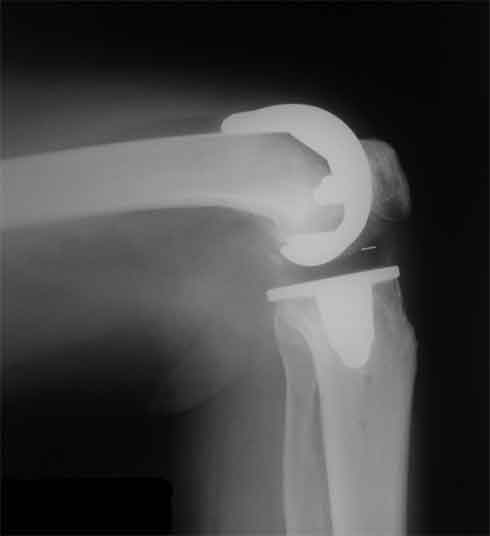

Стрессовый снимок

Оперирована пациентка 42 лет, избыточного веса. Выполнено б/ц протезированние коленного сустава эндопротезом LCS. Послеоперационный период гладкий, в срок 2 мес. после операции объем движений удовлетворительный, сгибание до острого угла, разгибание полное. В 3,5 мес. во время падения подвернула ногу, после чего появилась. клиника медиолатеральной нестабильности. В течении 3 недель фиксация в туторе. При повторном осмотре жалобы на дискомфорт в коленном суставе, «щелканье», неустойчивость в суставе. Вопросы/варианты дальнейшей тактики лечения пациентки.